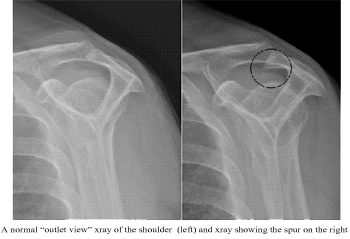

Spur: A spur is a small beak like downward projection from the bone (acromion), it can sometimes be a cause of impingement.

X-rays: X-ray may sometimes pick up a spur, which may be the cause of pain.